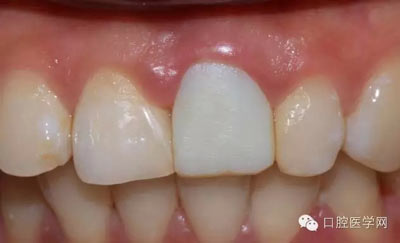

術(shù)前照

檢查:21金屬烤瓷冠修復(fù),顏色及形態(tài)與鄰牙不協(xié)調(diào),牙齦有輕微發(fā)黑,扣痛(-)、松動(dòng)度(-);11近中鄰面齲壞